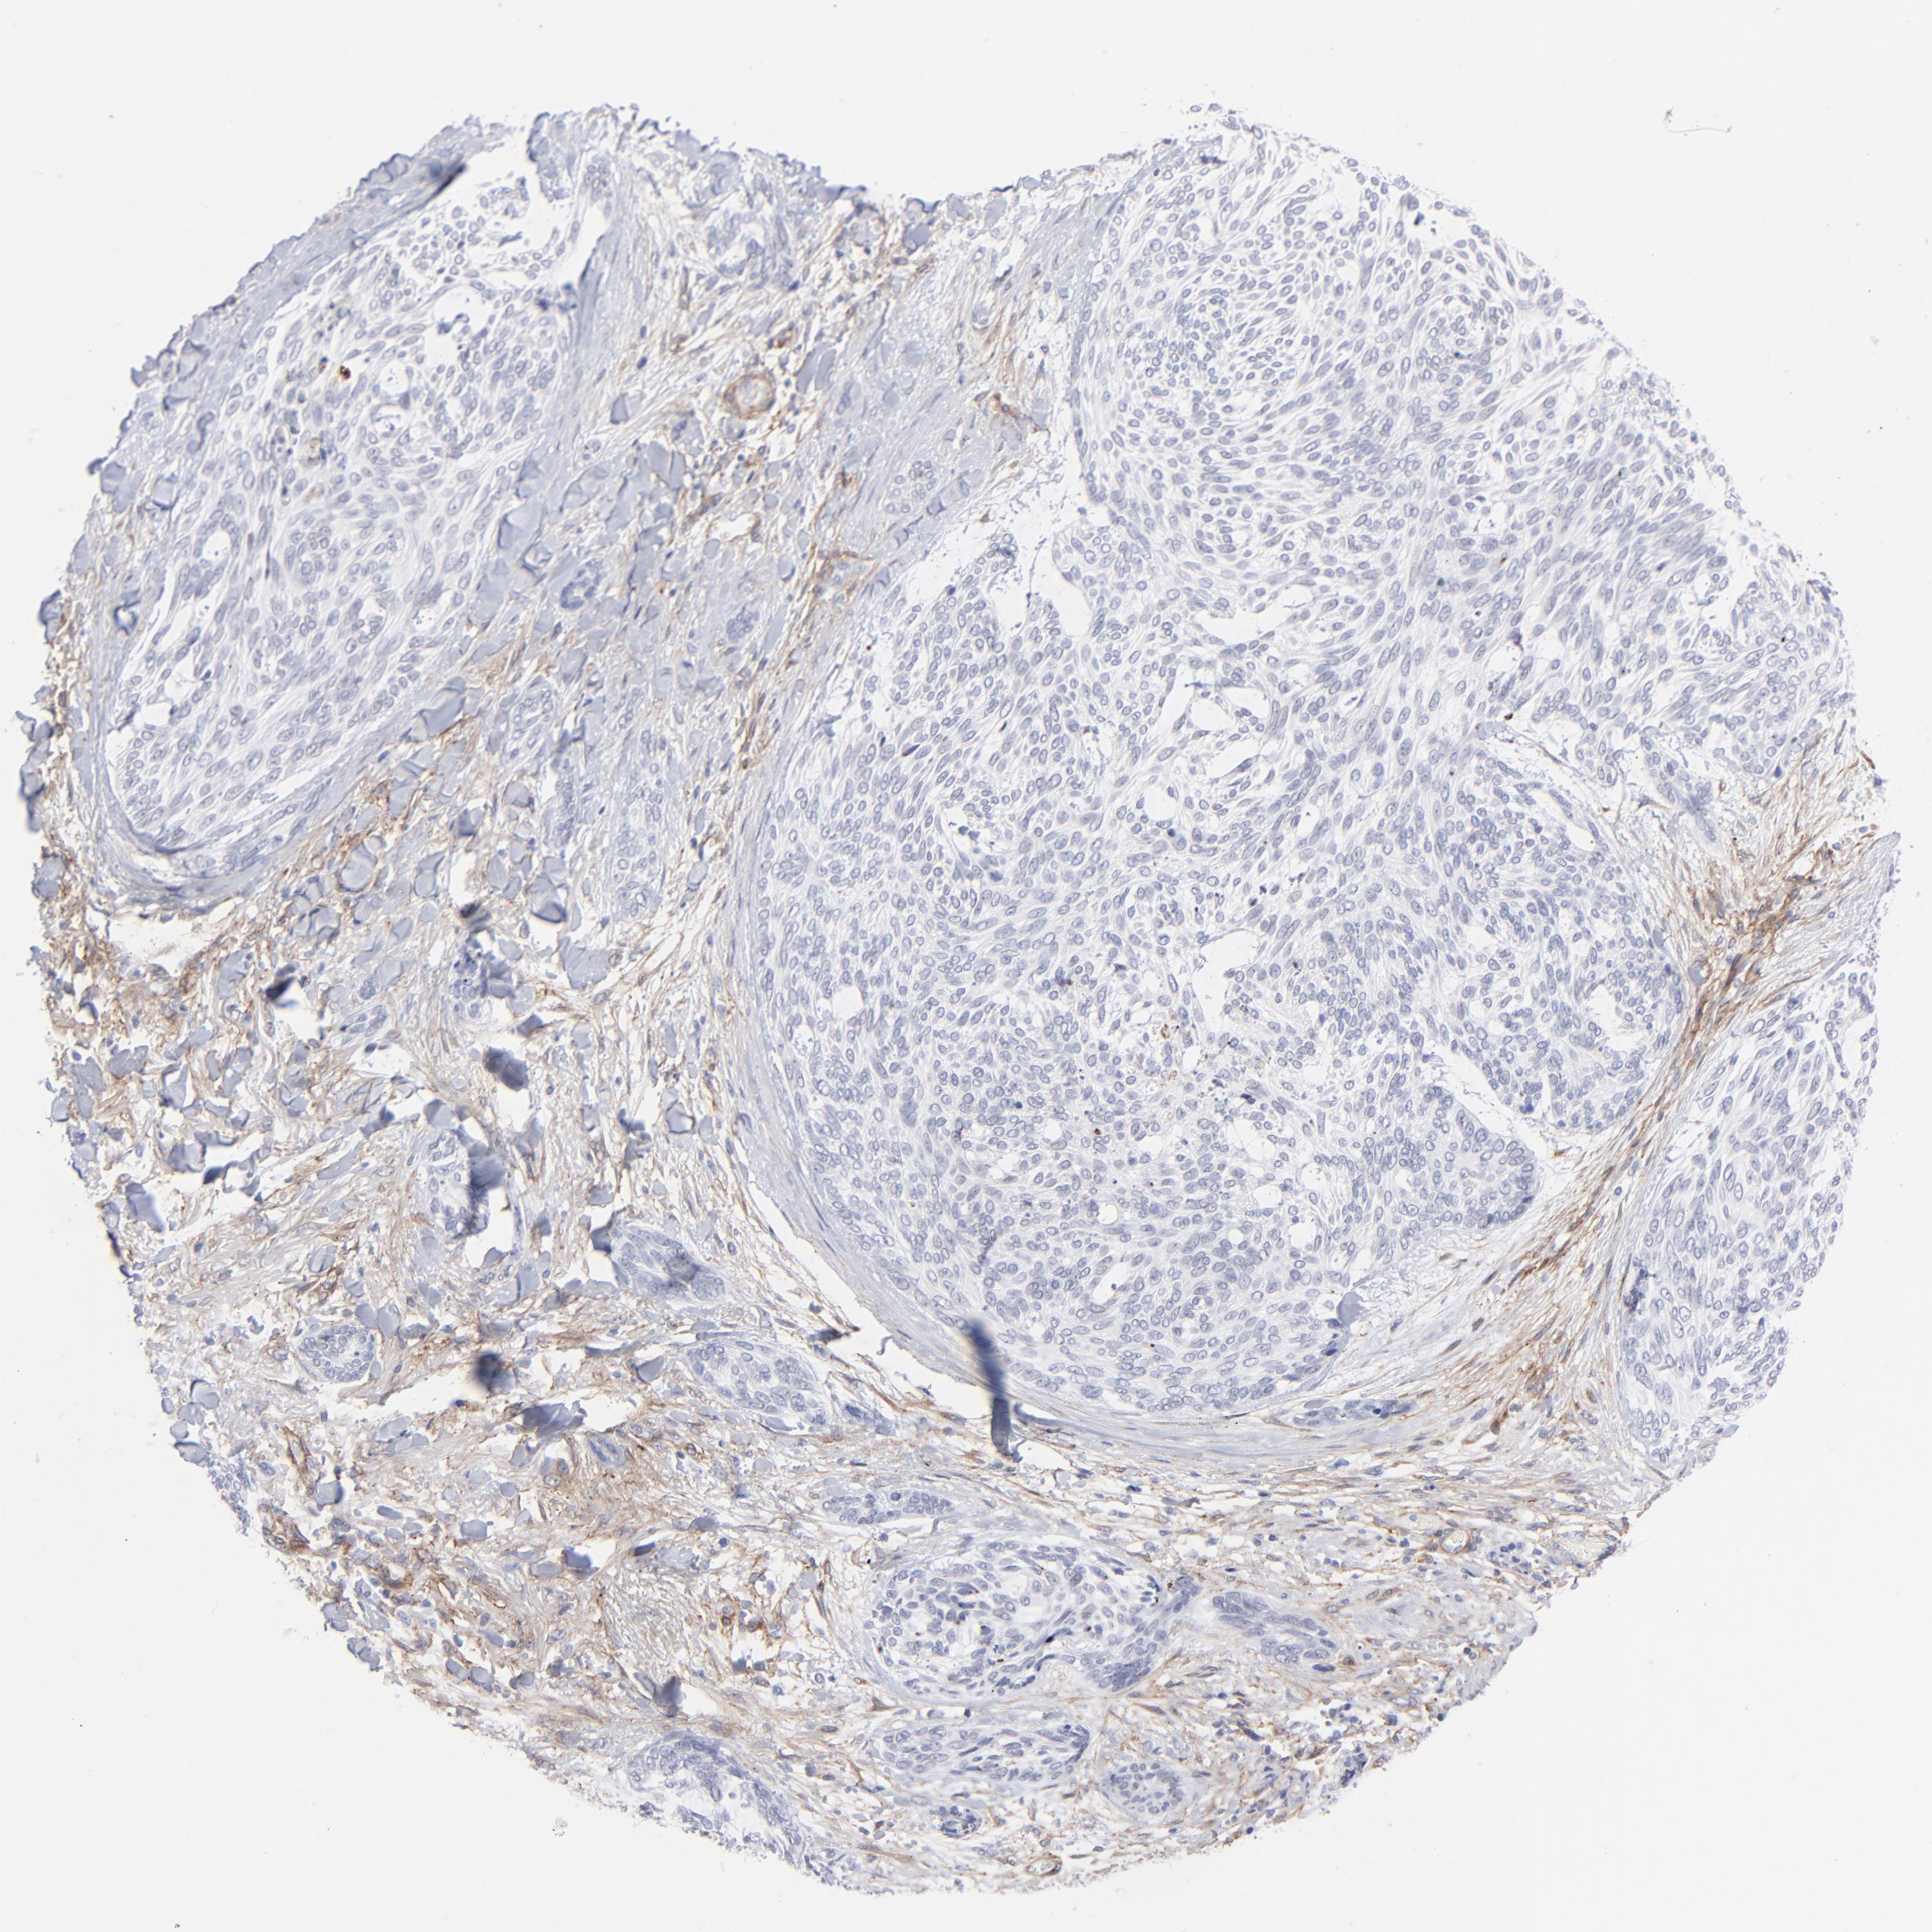

SKIN CANCER - Protein expressioni

A mouse-over function shows sample information and annotation data. Click on an image to view it in a full screen mode. Samples can be filtered based on level of antibody staining by selecting one or several of the following categories: high, medium, low and not detected. The assay and annotation is described here.

Antibody stainingi

Antibody staining in the annotated cell types in the current human tissue is reported as not detected, low, medium, or high, based on conventional immunohistochemistry profiling in selected tissues. This score is based on the combination of the staining intensity and fraction of stained cells.

Each image is clickable and will lead to virtual microscopy that enables deeper exploration of all samples and also displays staining intensity scores, fraction scores and subcellular localization as well as patient and tissue information for each sample.

Antibody CAB003842

Antibody CAB018144

Squamous cell carcinoma, NOS

Basal cell carcinoma

Squamous cell carcinoma in situ, NOS

Squamous cell carcinoma, metastatic, NOS